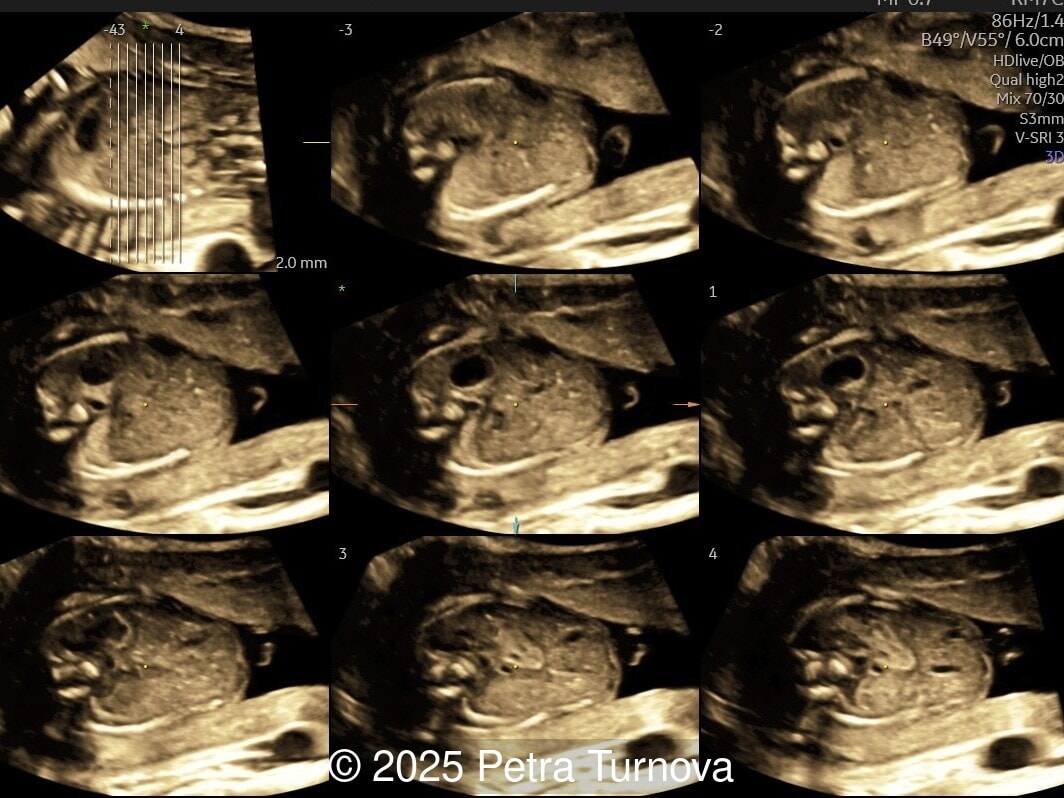

Ultrasound examination revealed abnormal subcutaneous tissue and abnormal nuchal fold highly suggestive of trisomy 21. In addition, a marked hepatomegaly was noted, with the liver appearing diffusely hyperechogenic. No ascites or signs of hydrops were present.

Given the constellation of findings, Trisomy 21 with associated hematologic involvement, most likely transient myeloproliferative disorder, was suspected. The patient underwent amniocentesis, which confirmed Trisomy 21. After multidisciplinary counseling, the patient opted for termination of pregnancy, which was performed at 20 weeks gestation. A fetal autopsy was performed. External examination confirmed facial dysmorphism characteristic of Down syndrome, including a flat nasal bridge and epicanthic folds. Internal examination revealed marked hepatosplenomegaly with the liver weighing approximately 2.5 times the expected weight for gestational age and demonstrated diffuse pale nodularity. Histopathologic examination showed massive extramedullary hematopoiesis with numerous immature megakaryoblasts, large atypical nuclei, and frequent mitotic figures within the hepatic sinusoids and portal areas. Similar infiltrates were present in the splenic red pulp and occasionally in the bone marrow, confirming the diagnosis of transient myeloproliferative disorder in association with Trisomy 21. This case underscores the importance of recognizing fetal hepatomegaly with dysmorphic features of Trisomy 21 as a potential marker of transient myeloproliferative disorder, prompting targeted cytogenetic testing and appropriate counseling.

From the prenatal diagnostic viewpoint, the combination of trisomy 21 and hepatosplenomegaly on ultrasound should prompt suspicion of transient myeloproliferative disorder [1,4]. The disease can manifest as fetal hepatosplenomegaly, hydrops fetalis, polyhydramnios, or placentomegaly [4,5]. The enlarged fetal liver, often hyperechogenic, reflects massive extramedullary hematopoiesis and infiltration by megakaryoblasts. Splenic enlargement and occasional ascites or pericardial effusion may accompany the presentation. Doppler studies may show increased middle cerebral artery peak systolic velocity due to fetal anemia [5,6]. Cytologically, peripheral blood and fetal liver aspirates reveal increased circulating blasts, often with megakaryoblastic morphology (irregular nuclei, cytoplasmic blebs, and platelet peroxidase positivity). Bone marrow may be normocellular or show hypocellularity with increased immature megakaryocytes [2].